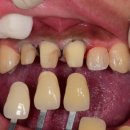

더이로운치과병원을 소개해드릴께요 많이 기다리 셨죠? 드뎌 오픈 했어요~♡ 제가 더 떨리고 기대되고... 전문기공소를 보유하고 있는 치과답게 더욱 빠르고 정확한 피드백으로 만족도가 높은 결과...

10년 이상 협업 중인 디지털 기공소와 함께 모든 케이스를 정밀하게 제작합니다. 즉, 보험이 적용되는 경우라도 기성 어버트먼트를 사용하는 일은 없습니다.이로운치과 임플란트 왜 이렇게까지...

임플란트 하나를 심더라도 최선을 다하는 원주 혁신도시, 관설동 이로운치과 입니다. 오늘은... 전문 기공소와 협업하여 심미적이고 기능적인 치아를 제작하는 데 최선을 다하고 있습니다. 인싸력이...